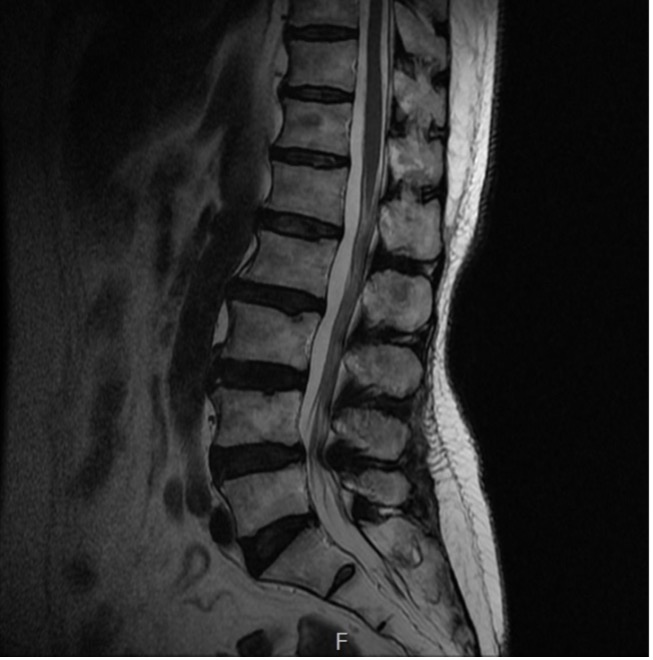

척추관협착증

척추관협착증이란

어떤 원인으로 척추 중앙의 척추관, 신경근관 또는 추간공이 좁아져 허리의 통증의 유발하거나 다리에 여러 복합적인 신경증세를 일으키는 질환

입니다.

디스크를 구성하는 수핵과 섬유륜에 퇴행성 변화가 일어나고 척추관을 구성하는 뼈와 인대 등이 두꺼워져 척추 뼈가 어긋나는 경우 척추 신경을 눌러 통증을 일으킵니다.